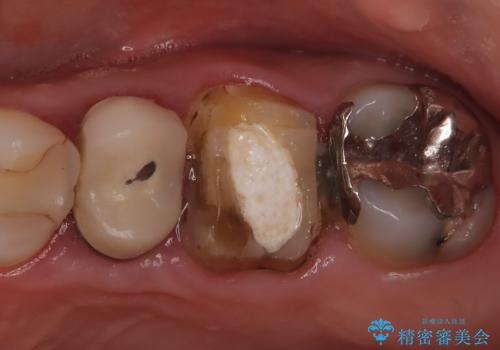

不適な樹脂の詰め物 被せ物で被覆

担当医 岡田康成